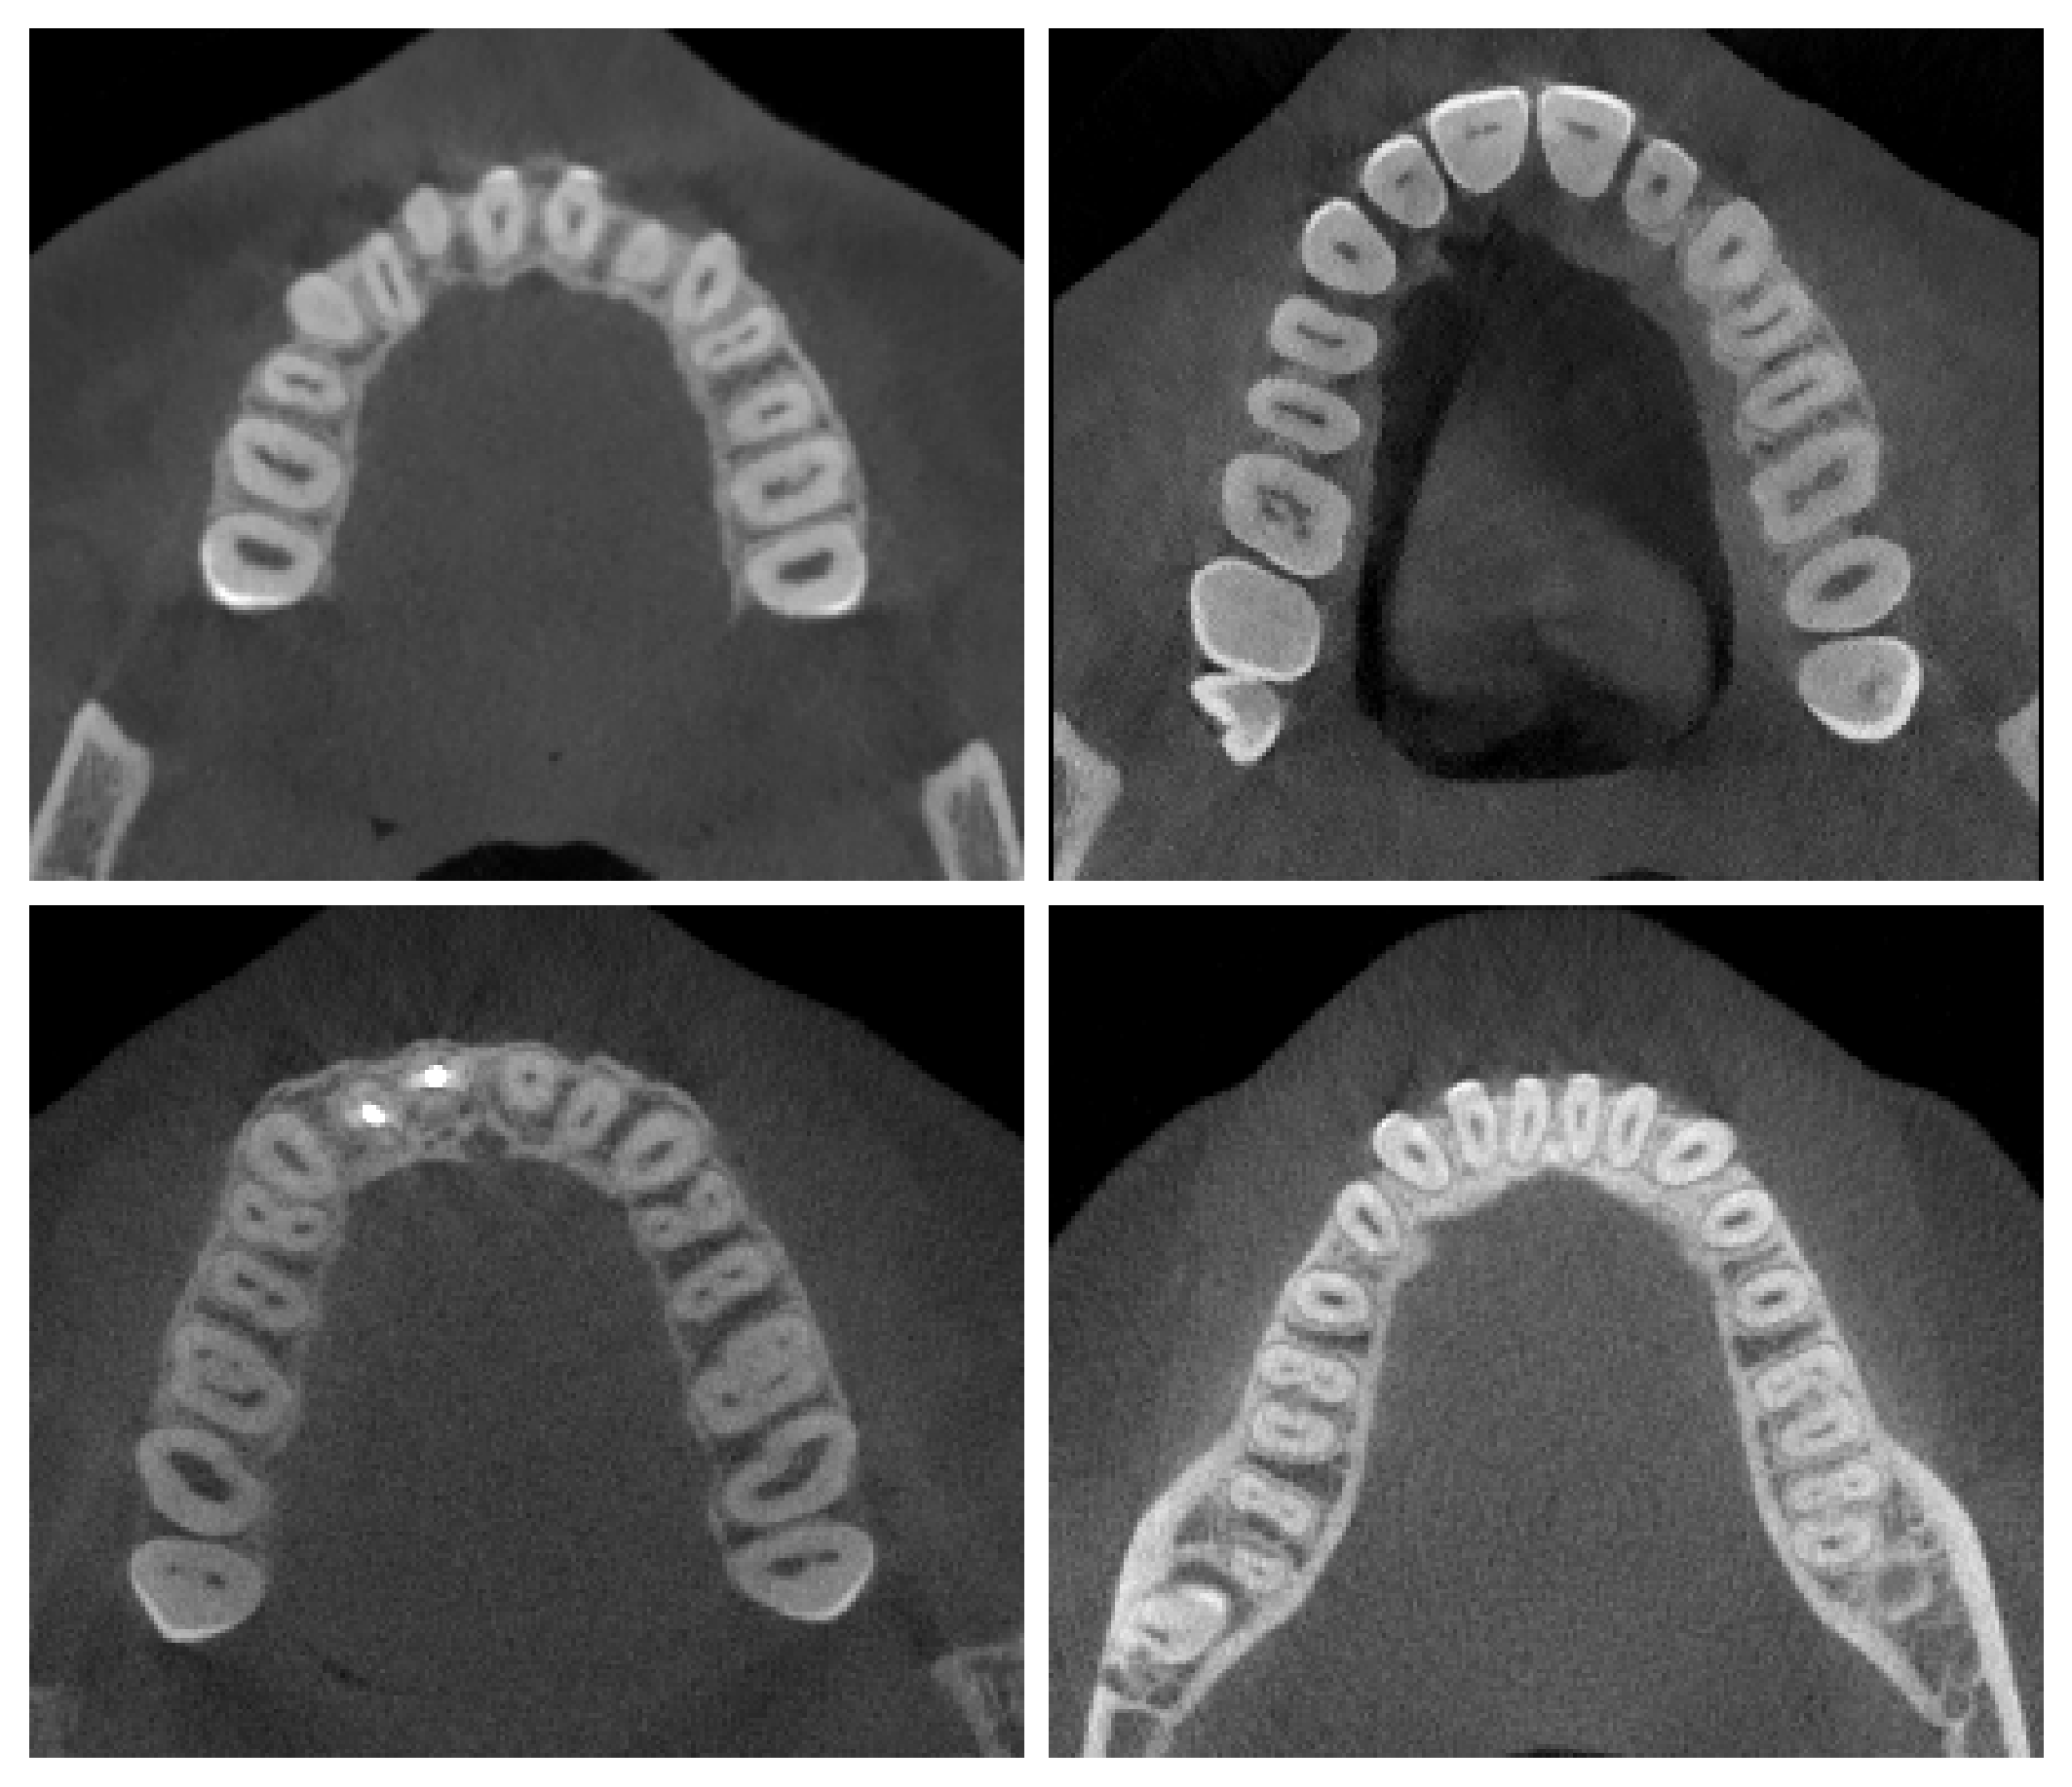

Refer to caption

Figure 0.A.1: Samples from our in-house CBCT scans test set are shown: the first row represents scans from center A, and the second from center B. We release these scans for the community to enhance research in the field.

We utilize 20 in-house CBCT scans collected from two medical centers, referred to as Center A and Center B (scan examples are shown in Fig. 0.A.1). Both datasets come from Warsaw, Poland. The data consist of anonymized CBCT volumes and voxel-wise segmentation masks for 3D tooth structures. The use of the data was approved by the Institutional Review Board (IRB Approval ID: OKW-623/2022). Center A provides 11 scans, while Center B contributes 9 scans. The scans were acquired using the Carestream CS 9600 and i-CAT 17-19 imaging systems, with slice thicknesses of 0.150.150.15 mm/px and 0.20.20.2 mm/px, respectively.